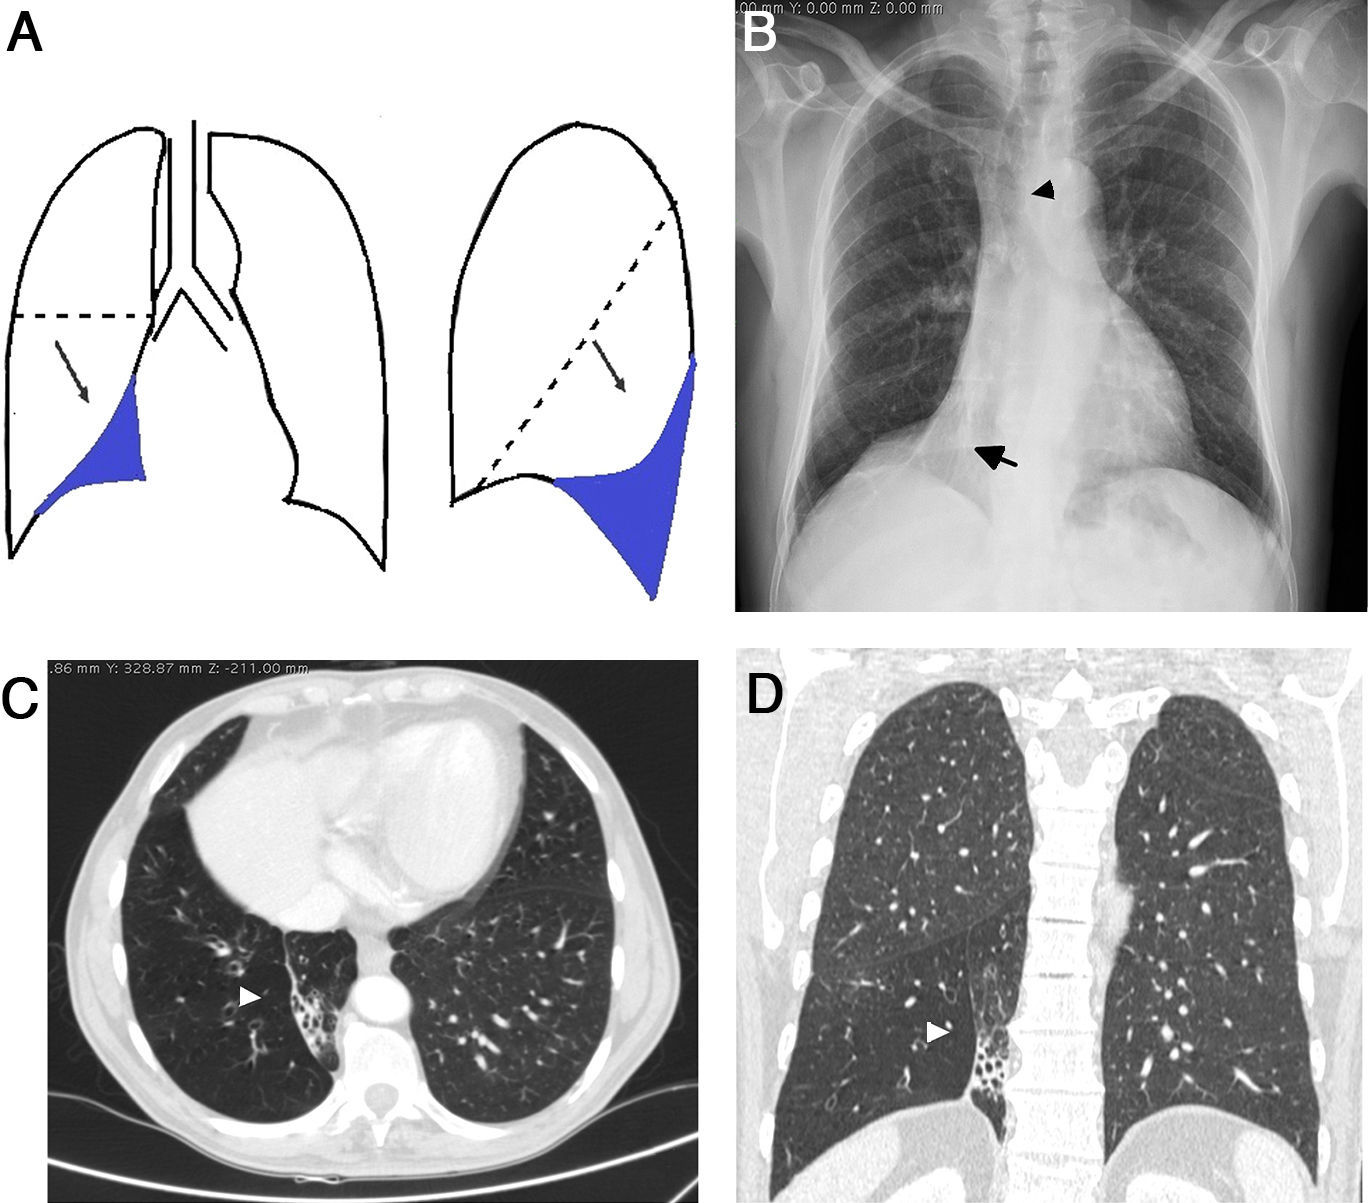

Atelectasis is an important indicator of potentially severe underlying disease that must be diagnosed as early as possible. One of the most common mechanisms is the reabsorption of air distal to respiratory tract obstruction. The chest X-ray is an excellent tool to diagnose atelectasis, and it is especially useful for ruling out central bronchial obstructions (e.g., from endobronchial tumors). If the signs of volume loss are not recognized correctly, the diagnosis and treatment can be delayed. This article describes the main findings of lobar atelectasis on chest X-rays and their correlations with CT findings, including the classic signs described in the literature and other, less known and sometimes subtle signs.